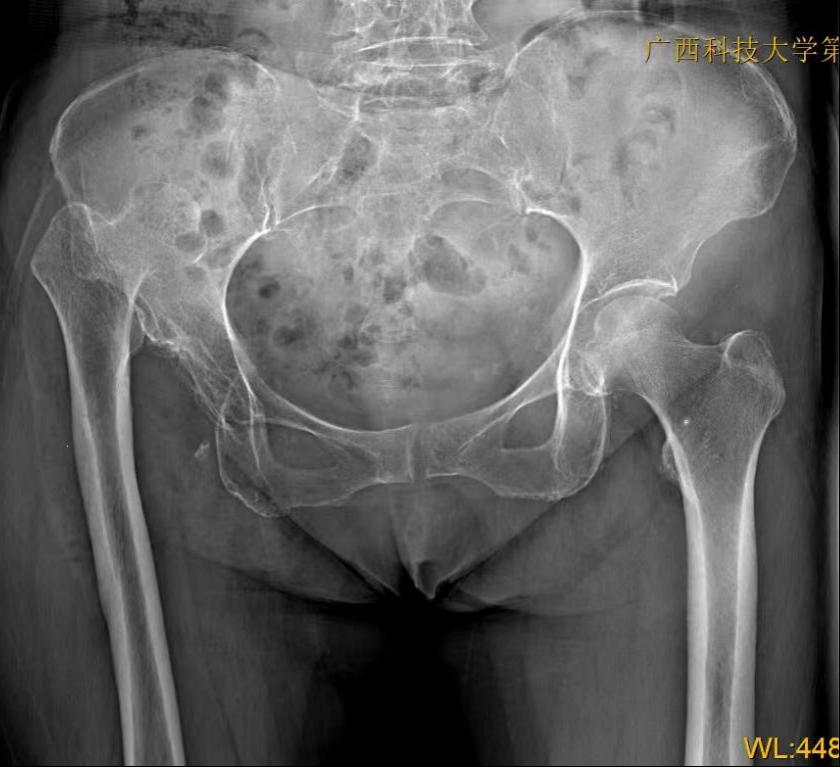

范阿姨入院检查后,明确诊断为右侧发育性髋关节发育不良(DDH),高脱位CroweIV型(最严重类型),右下肢较左下肢短缩8cm,属于极高难度髋部畸形病例,手术风险高、矫形难度大。

术前